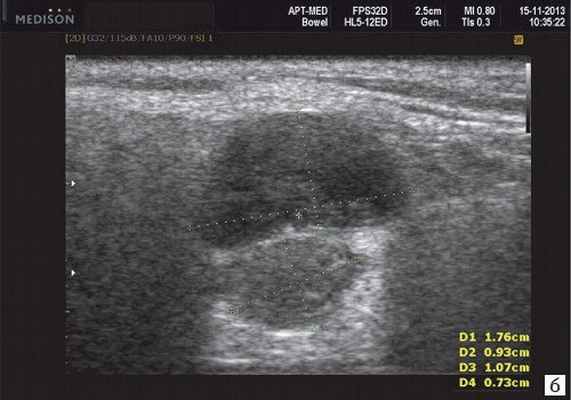

Рис. 3. Сиаладенит правой поднижнечелюстной слюнной железы.

Сиаладениты - большая группа полиэтиологических воспалительных заболеваний СЖ (рис. 3). Первичные сиаладениты - сиаладениты, рассматриваемые в качестве самостоятельных заболеваний (например, эпидемический паротит). Вторичные сиаладениты - сиаладениты, являющиеся осложнениями или проявлениями других заболеваний (например, сиаладенит при гриппе). Эхографическая картина при разной этиологии малоспецифична. Этиология имеет клиническое значение в процессе определения тактики лечения.